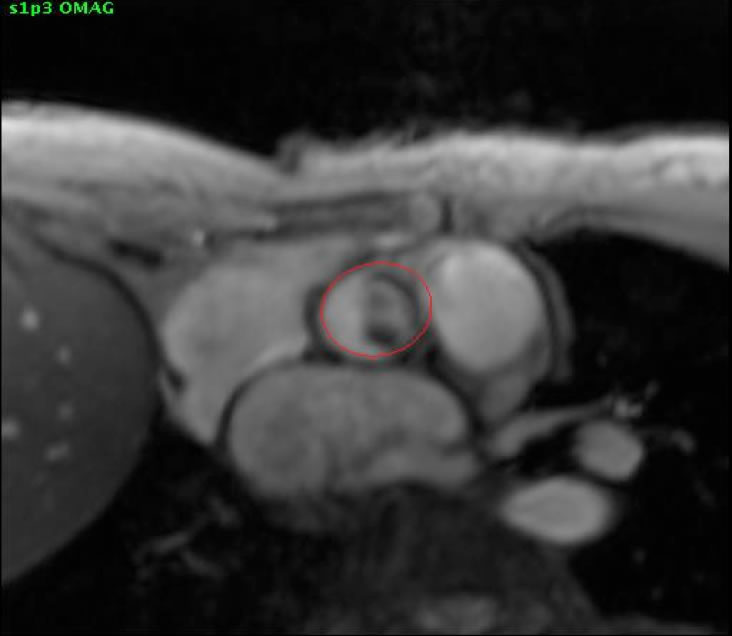

From cardiacmri.com

Mitral regurgitation Cardiac MRI Ejection Fraction Mitral Regurgitation Mitral regurgitation is a heart condition characterized by the incomplete closure of the mitral valve, leading to the backflow of blood from the left ventricle into the left atrium during systole. This expert consensus decision pathway emphasizes that recognition of mr should prompt. Mitral regurgitation (mr) is a complex valve lesion that can pose significant management challenges. Moderate mr is. Ejection Fraction Mitral Regurgitation.